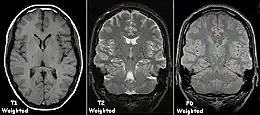

| Spin echo | T1 weighted | T1 | Measuring spin–lattice relaxation by using a short repetition time (TR) and echo time (TE). |

Standard foundation and comparison for other sequences |

| T2 weighted | T2 | Measuring spin–spin relaxation by using long TR and TE times |

| Proton density weighted | PD | Long TR (to reduce T1) and short TE (to minimize T2).[7] | Joint disease and injury.[8]

Each tissue returns to its equilibrium state after excitation by the independent relaxation processes of T1 (spin-lattice; that is, magnetization in the same direction as the static magnetic field) and T2 (spin-spin; transverse to the static magnetic field). To create a T1-weighted image, magnetization is allowed to recover before measuring the MR signal by changing the repetition time (TR). This image weighting is useful for assessing the cerebral cortex, identifying fatty tissue, characterizing focal liver lesions, and in general, obtaining morphological information, as well as for post-contrast imaging. To create a T2-weighted image, magnetization is allowed to decay before measuring the MR signal by changing the echo time (TE). This image weighting is useful for detecting edema and inflammation, revealing white matter lesions, and assessing zonal anatomy in the prostate and uterus.